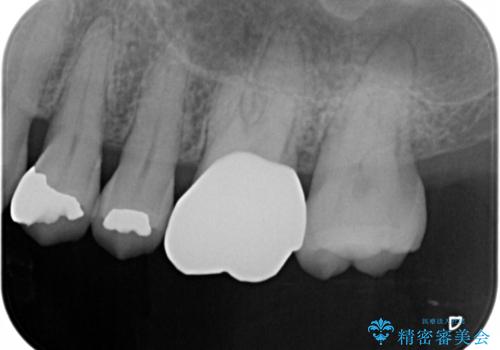

- 以前に異なる種類の材料で継ぎ接ぎ状態で修復されており、隙間のところから虫歯が再発していました。歯の手前側と後方及び内側に亀裂も入っていたため、将来的な虫歯再発のリスク及び歯の破折リスクを最小限にとどめるよう、被せものにて治療を行いました。

適合不良の補綴物は二次的な虫歯発生のリスクが高まります。

自費診療で用いられる材料は保険適応の材料に比べて、より精密で適合の良い被せ物作ることができるため、長期的な虫歯のリスクを大幅に減らすことが可能です。